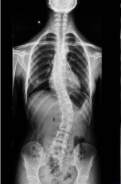

脊柱侧弯是一种常见的骨骼问题,在站姿下,不管从正面或背面看,正常的脊椎排列应该是身体左右两边对称,并且正常的脊椎排列从上到下是呈一直线的。

如果在站姿下看到脊柱向身体的任何一边弯曲歪斜,就是有可能是脊柱侧弯,左右手臂与躯干之间的空隙不对称,右侧肩膀较高。不过,大部分的脊柱侧弯并不只有单一平面的左右倾斜,通常会伴随着脊椎旋转,往往也会影响到肩胛骨的动作,导致肩关节的活动度受限。

第二步是需要家长带小孩到医院拍摄全脊柱的X光片,确定小孩脊柱侧弯的度数。在医院做的全脊柱(颈胸腰骶椎)X光片,可直观得出是否有脊柱侧弯、侧弯度数。这是目前对脊柱侧弯最确切的诊断方式,以cobb角10度作为标准,如果这个角度大于10度,就要诊断脊柱侧弯了。